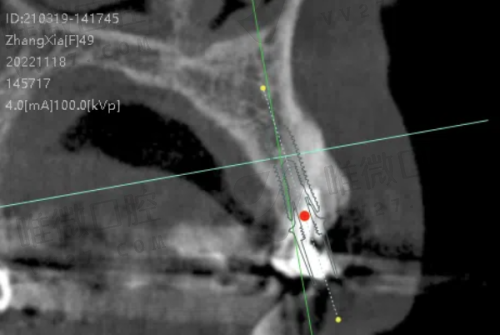

提到丽齿传世口腔,就不能不说它家的数字化种植和隐形矫正技术。它在种植领域使用的是目前主流的数字导航式种植技术,主要合作品牌包括瑞士ITI、诺贝尔、韩国奥齿泰、纽百特等。医生通过CBCT三维扫描,先在电脑上“预演”种植过程,再携带导板真正进入口腔操作,全程精细定位、安心微创,即使是骨量不足的疑难种植也能稳稳拿下。